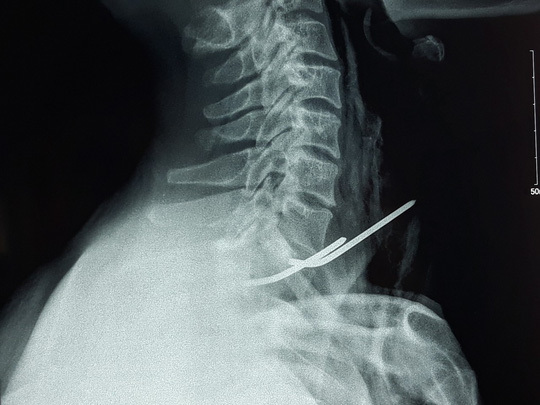

Sau khi hội chẩn, các bác sĩ quyết định phương án giải áp tĩnh mạch cửa: phẫu thuật bắc cầu tĩnh mạch cửa để chuyển hướng lượng máu từ tĩnh mạch cửa vào các tĩnh mạch khác. Dùng 1 đoạn tĩnh mạch cảnh trong ở cổ làm cầu bắc ngang giải áp cho tĩnh mạch cửa qua tĩnh mạch mạc treo tràng trên ở ruột.

ThS BS Tạ Huy Cần, Trưởng khoa Ngoại tổng quát cho biết, đây là kỹ thuật phẫu thuật cực kỳ khó và tỉ mĩ vì tĩnh mạch cực kỳ mỏng và nhỏ, dưới 0,1 mm, đòi hỏi êkíp phẫu thuật phải hiểu ý nhau, tinh tế, chỉ cần đi lệch hoặc thao tác thiếu chính xác sẽ làm rách mạch máu, phải nối lại chắc chắn không tốt và gây ảnh hưởng đường máu đi.